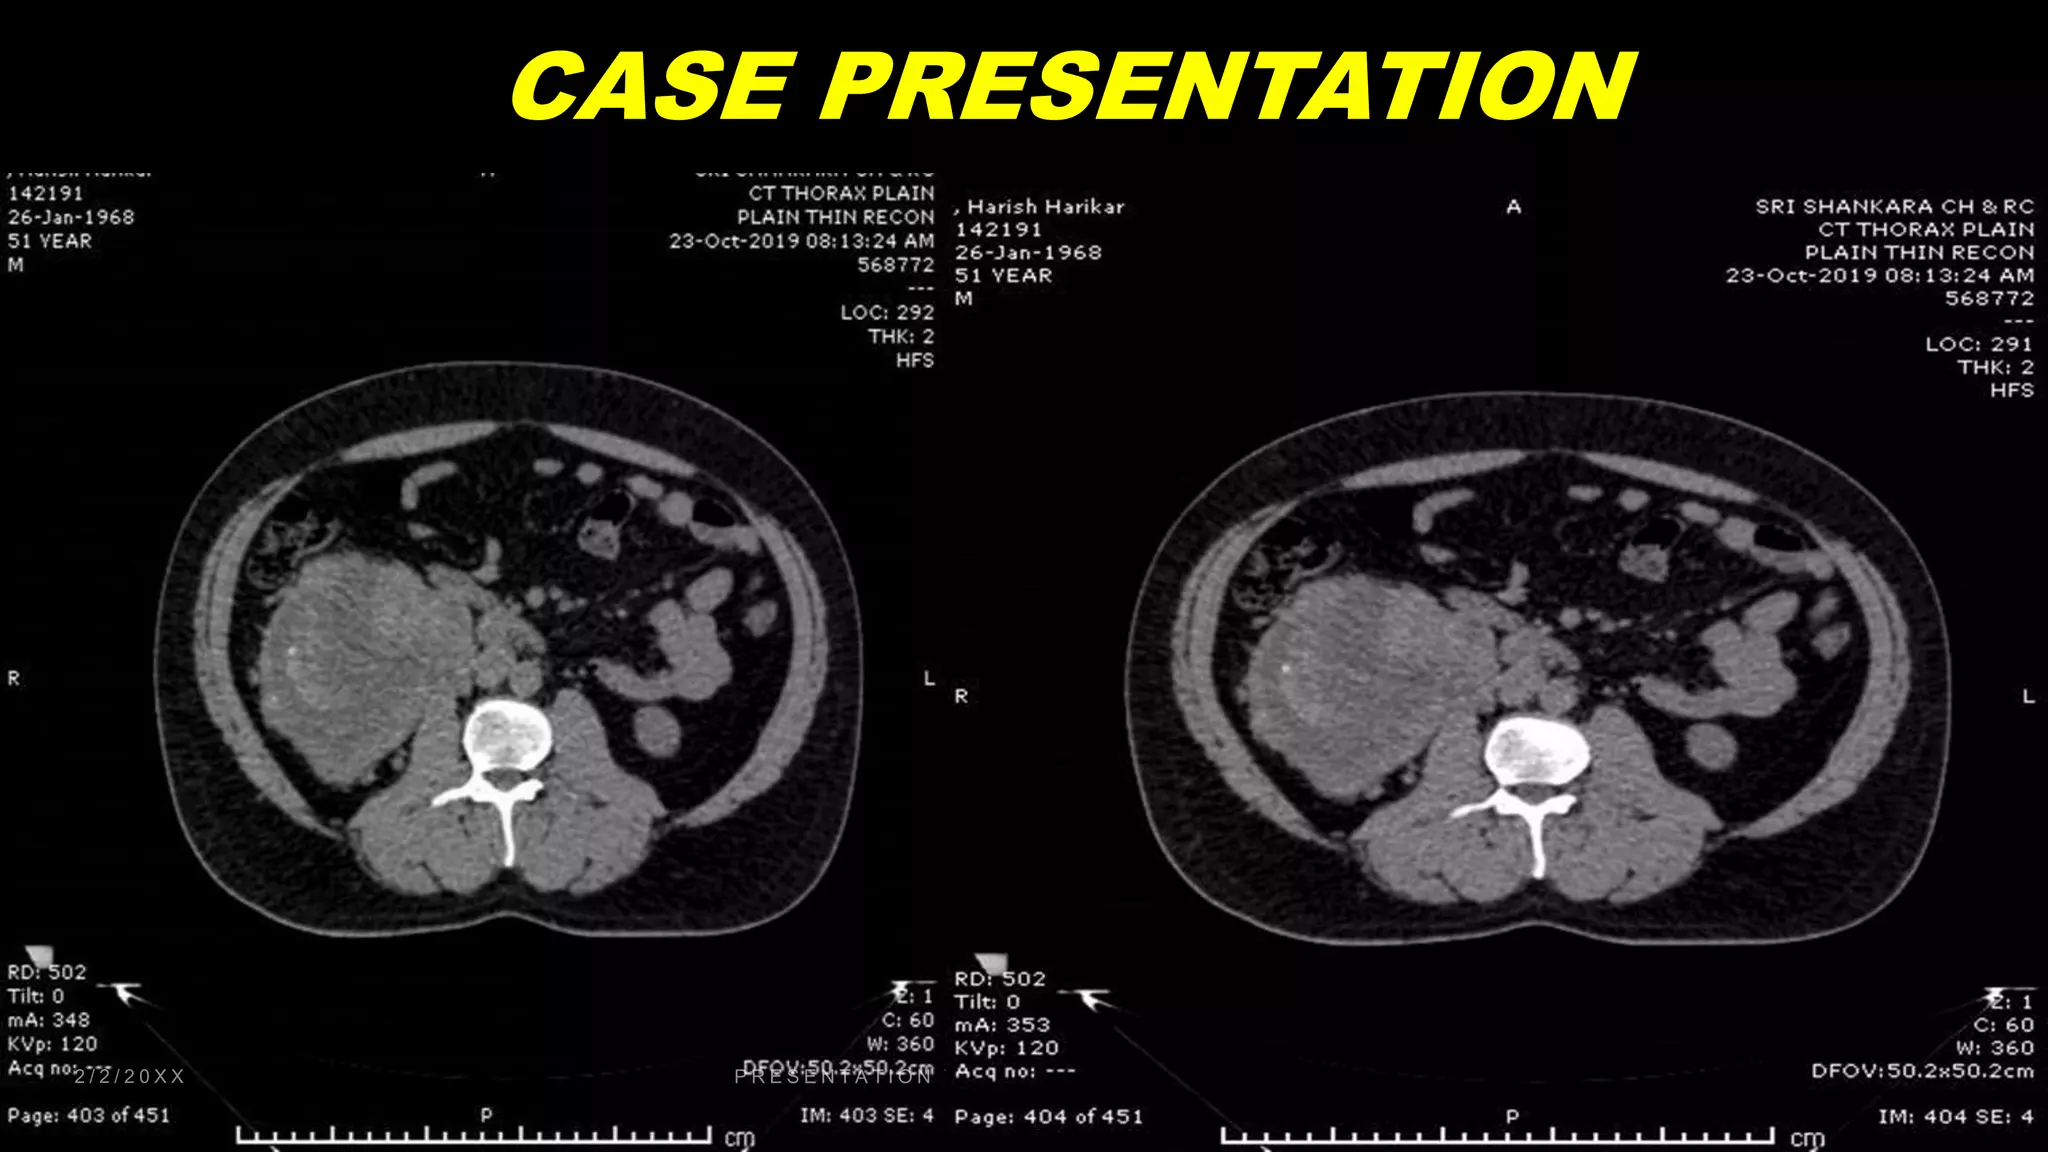

CASE PRESENTATION